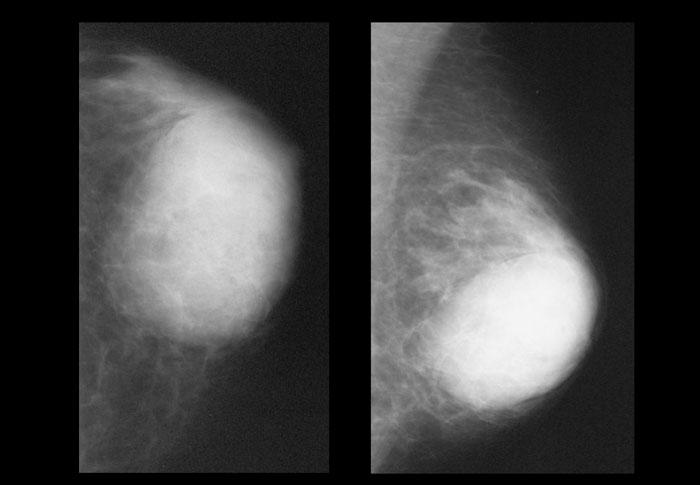

Bên trái là hai ví dụ về nhũ ảnh nam giới bình thường.

Hình bên trái cho thấy da bình thường, núm vú và một lượng nhỏ mô liên kết phía sau núm vú.

Hình bên phải cho thấy nhiều mô liên kết hơn một chút, nhưng vẫn trong giới hạn bình thường.